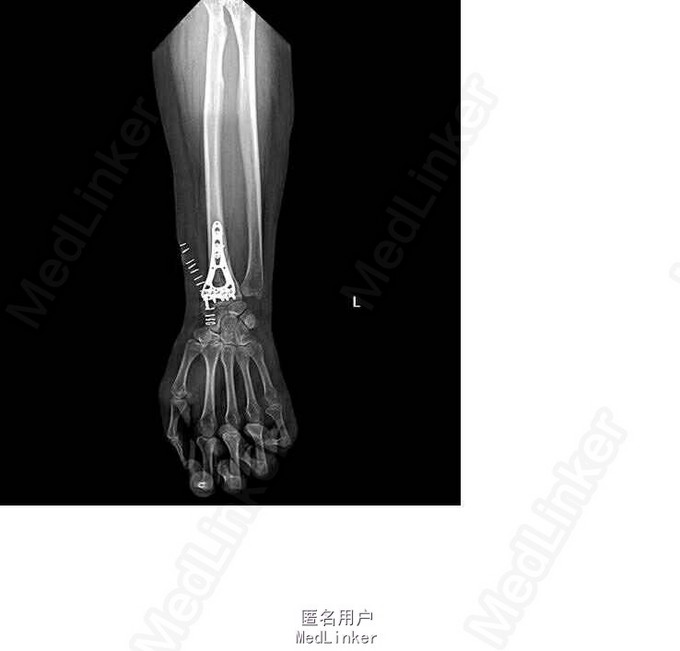

诊断:右侧桡骨远端骨折(barton骨折) 双手皮肤软组织挫伤 行左桡骨远端骨折切开复位内固定术

术后恢复良好